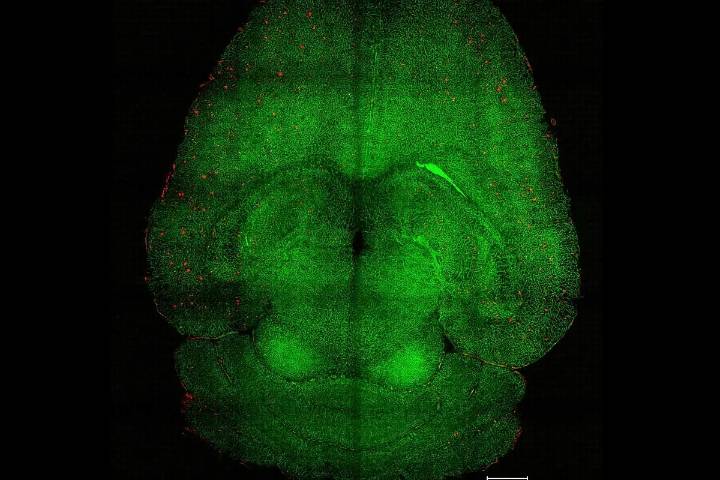

Un innovador experimento explora la posibilidad de tratar el alzhéimer modulando la barrera hematoencefálica, en lugar de con las estrategias actuales. La investigación, codirigida por científicos del Instituto de Bioingeniería de Cataluña (IBEC) y del Hospital West China de la Universidad de Sichuan , ha conseguido en el modelo murino de la enfermedad, el aclaramiento de las placas de amiloide beta y la recuperación cognitiva mediante unas nanopartículas que se dirigen la vasculatura cerebral.

Para ello, bastaron tres inyecciones de las nanopartículas , que actuaron como sustancias bioactivas, no como meros vectores de una molécula terapéutica. Estos "fármacos supramoleculares" restablecieron el fu